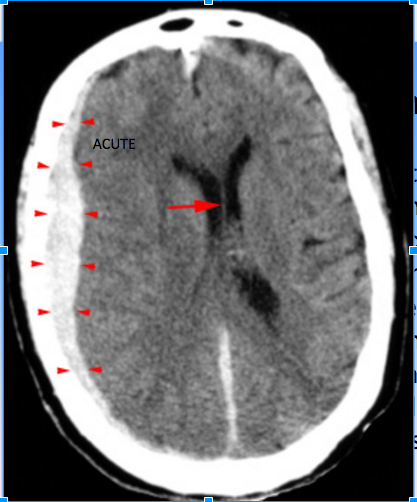

- What is the injury to in a subdural hematoma?

- Where does blood collect?

- Tearing of bridging veins from deceleration and acceleration or rotational forces

- Blood collects in the space between the arachnoid mater and the dura mater

Subdural Hematoma CT has the following characteristics: 3

- Crescent shaped

- Hyperdense, may contain hypodense foci due to serum, CSF or active bleeding

- Does not cross dural reflections

High density, crescent shaped hematoma (arrowheads)

overlying the right cerebral hemisphere. Whats important to note in this image?

Subacute subdural hematoma (arrowheads). Whats important to note about this CT?

Note the compression of

gray and white matter in the left hemisphere due to the mass effect.